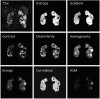

Magnetic resonance imaging (MRI) examinations provide high-resolution information about the anatomic structure of the kidneys and are used to measure total kidney volume (TKV) in patients with Autosomal Dominant Polycystic Kidney Disease (ADPKD). Height-adjusted TKV (HtTKV) has become the gold-standard imaging biomarker for ADPKD progression at early stages of the disease when estimated glomerular filtration rate (eGFR) is still normal. However, HtTKV does not take advantage of the wealth of information provided by MRI. Here we tested whether image texture features provide additional insights into the ADPKD kidney that may be used as complementary information to existing biomarkers. A retrospective cohort of 122 patients from the Consortium for Radiologic Imaging Studies of Polycystic Kidney Disease (CRISP) study was identified who had T2-weighted MRIs and eGFR values over 70 mL/min/1.73m2 at the time of their baseline scan. We computed nine distinct image texture features for each patient. The ability of each feature to predict subsequent progression to CKD stage 3A, 3B, and 30% reduction in eGFR at eight-year follow-up was assessed. A multiple linear regression model was developed incorporating age, baseline eGFR, HtTKV, and three image texture features identified by stability feature selection (Entropy, Correlation, and Energy). Including texture in a multiple linear regression model (predicting percent change in eGFR) improved Pearson correlation coefficient from -0.51 (using age, eGFR, and HtTKV) to -0.70 (adding texture). Thus, texture analysis offers an approach to refine ADPKD prognosis and should be further explored for its utility in individualized clinical decision making and outcome prediction.